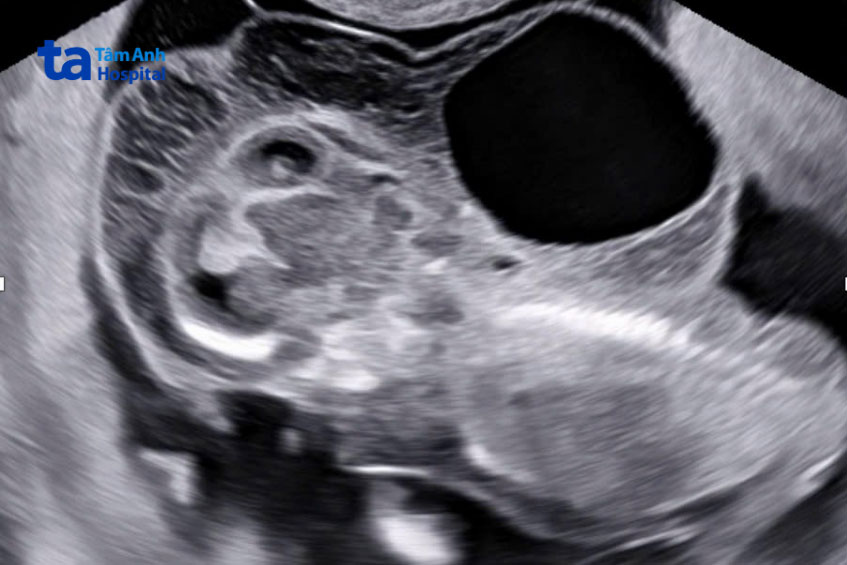

Một số dấu hiệu của bệnh có thể được phát hiện ngay từ khi thai nhi còn trong bụng mẹ, đặc biệt qua các xét nghiệm sàng lọc trước sinh như siêu âm, NIPT, xét nghiệm nhiễm sắc thể từ tế bào máu ngoại vi,… Những dấu hiệu trong thai kỳ bao gồm:

Nếu có bất kỳ dấu hiệu nào của hội chứng Turner trong thai kỳ hoặc trong khi trẻ ở giai đoạn sơ sinh, việc thăm khám và chẩn đoán kịp thời là rất quan trọng. Khi siêu âm tại các mốc thai kỳ quan trọng, nếu nhận thấy thai nhi có sự phát triển bất thường như chất dịch dày xung quanh vùng cổ của thai nhi, sự phát triển không đồng đều của các cơ quan trong cơ thể,… chị em nên tham khảo ý kiến của bác sĩ để được hướng dẫn thực hiện các xét nghiệm cần thiết. (3)

Chẩn đoán trước sinh có thể được thực hiện thông qua siêu âm thai, xét nghiệm máu, NIPT, chọc ối, lấy mẫu nhung mao màng đệm,… Những phương pháp này có thể phát hiện các dấu hiệu sớm của căn bệnh này bao gồm các chất dịch tích tụ nhiều ở xung quanh vùng cổ của thai nhi và sự phát triển bất thường của các cơ quan trong cơ thể như dị tật về tim mạch, thận,…